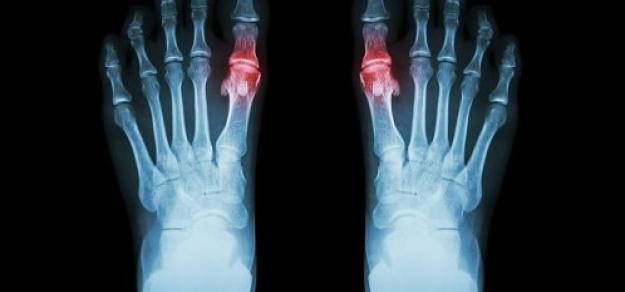

En pacientes con gota y sin enfermedad coronaria, el uso prolongado de alopurinol protege contra el primer síndrome coronario agudo (SCA) en comparación con los no usuarios. Por el contrario, los iniciadores del alopurinol, que posiblemente tenían más inflamación sistémica, tenían un mayor riesgo de SCA por primera vez en comparación con los usuarios a largo plazo. BMJ Open, 27 de febrero de 2025

En este estudio observacional se comparó el inicio de alopurinol para la gota acompañado de profilaxis con colchicina o con AINE versus alopurinol sin profilaxis asociada. Los eventos adversos fueron más comunes cuando se inició alopurinol con profilaxis, particularmente la aparición de diarrea con el uso de colchicina. Otros eventos fueron poco comunes, lo que brinda tranquilidad a los pacientes y a los médicos para permitir la toma de decisiones compartida. Annals of the Rheumatic Diseases, octubre de 2023.